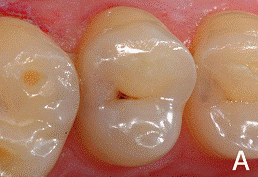

При этой форме кариозного процесса целостность

эмалево-дентинного соединения нарушается при этом зондирование границы

болезненно, однако под полостью зуба сохраняется достаточно толстый слой

дентина. При осмотре зуба обнаруживается неглубокая кариозная полость,

заполненная размягчённым, пигментированным дентином, что определяется при

Перкуссия и пальпация зуба безболезненно.

Термодиагностика чаще всего безболезненна или кратковременно болезненна. На

рентгенограмме определяется кариозная полость средней глубины не сообщающаяся с

полостью зуба. Локализация процесса чаще всего в фиссурах, на аппроксимальных

поверхностях и в пришеечной области.